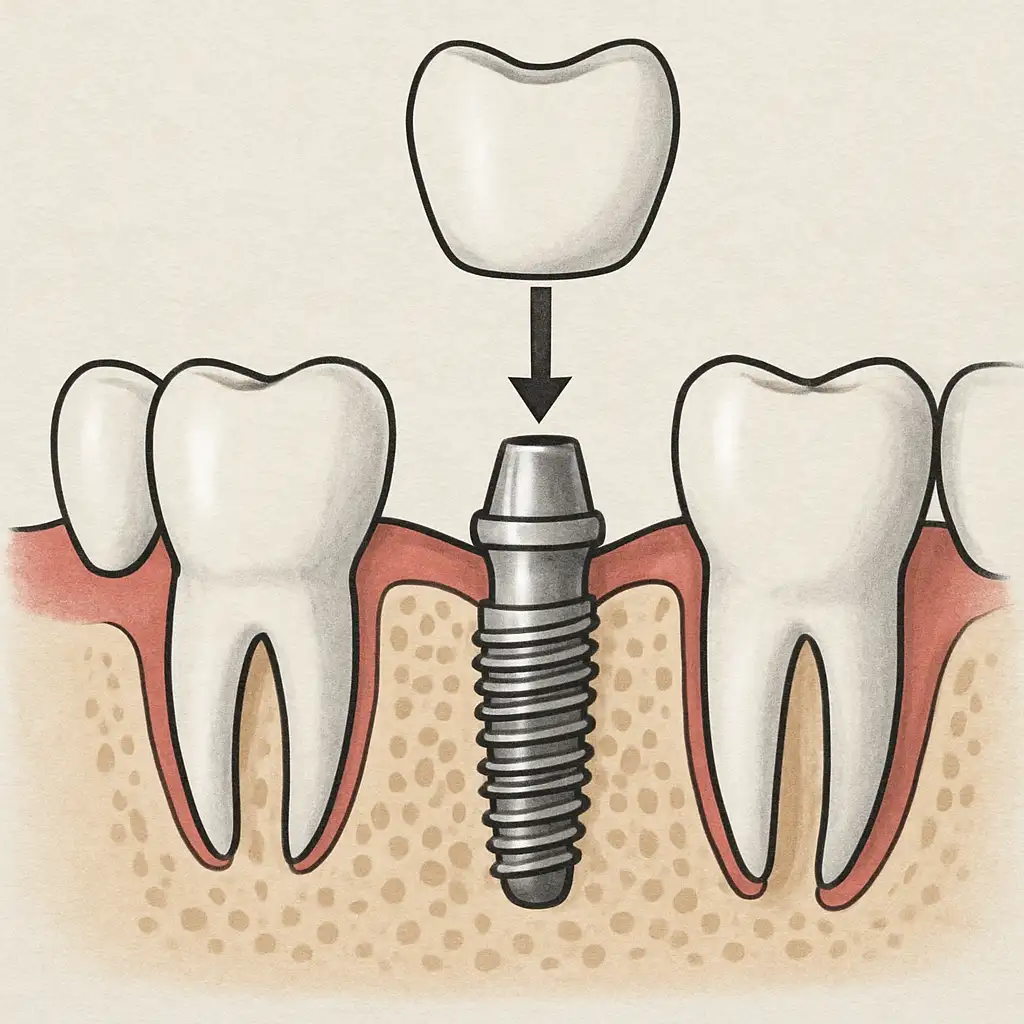

Can you go from wearing dentures to getting implants If you’ve been wearing dentures for a while, you might be wondering if it’s possible to switch to dental implants. The good news is, yes, it is possible! Transitioning from dentures to implants can offer more comfort, better functionality, and improved confidence. Implants can mimic the […]